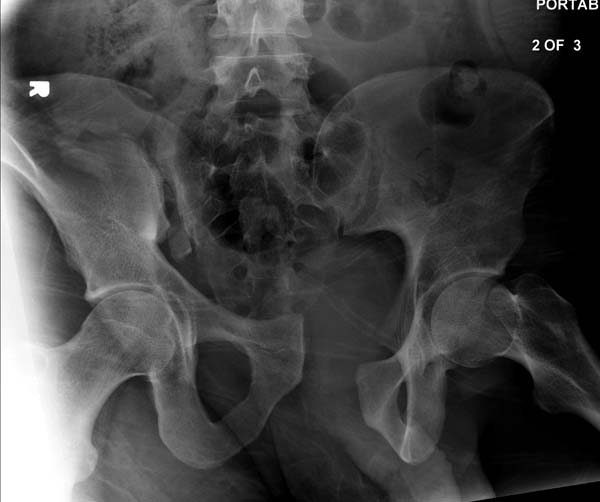

“При поступлении обследована (обзорный таза + вход в таз)”

До операции желательно выставить все стандартные снимки: обзорный таза, вход + выход. А популярный у всех 3Д используется только для общего обзора, но не для детального изучения. Обычно КТ “для диагностики-стандарт, а послеоперационно - дополнительный расход”. Лучше обычные рентген-снимки, но бывают исключения, когда на снимке имеются неясности, например, винт через сакральный форамен или через сустав!

Перелом заднего отдела крыла подвдошной кости доказывает, что задние связочные элементы подвздошно- крестцового сочленения интактны, и такой перелом известен как “Сrescent fracture’. Переломы разделяется на 4 типа, и до фиксации надо хорошо изучить топографию перелома, иначе винт может попасть в линию перелома и не удержать фиксацию.

Здесь примеры фиксации с различными вариантами.... .